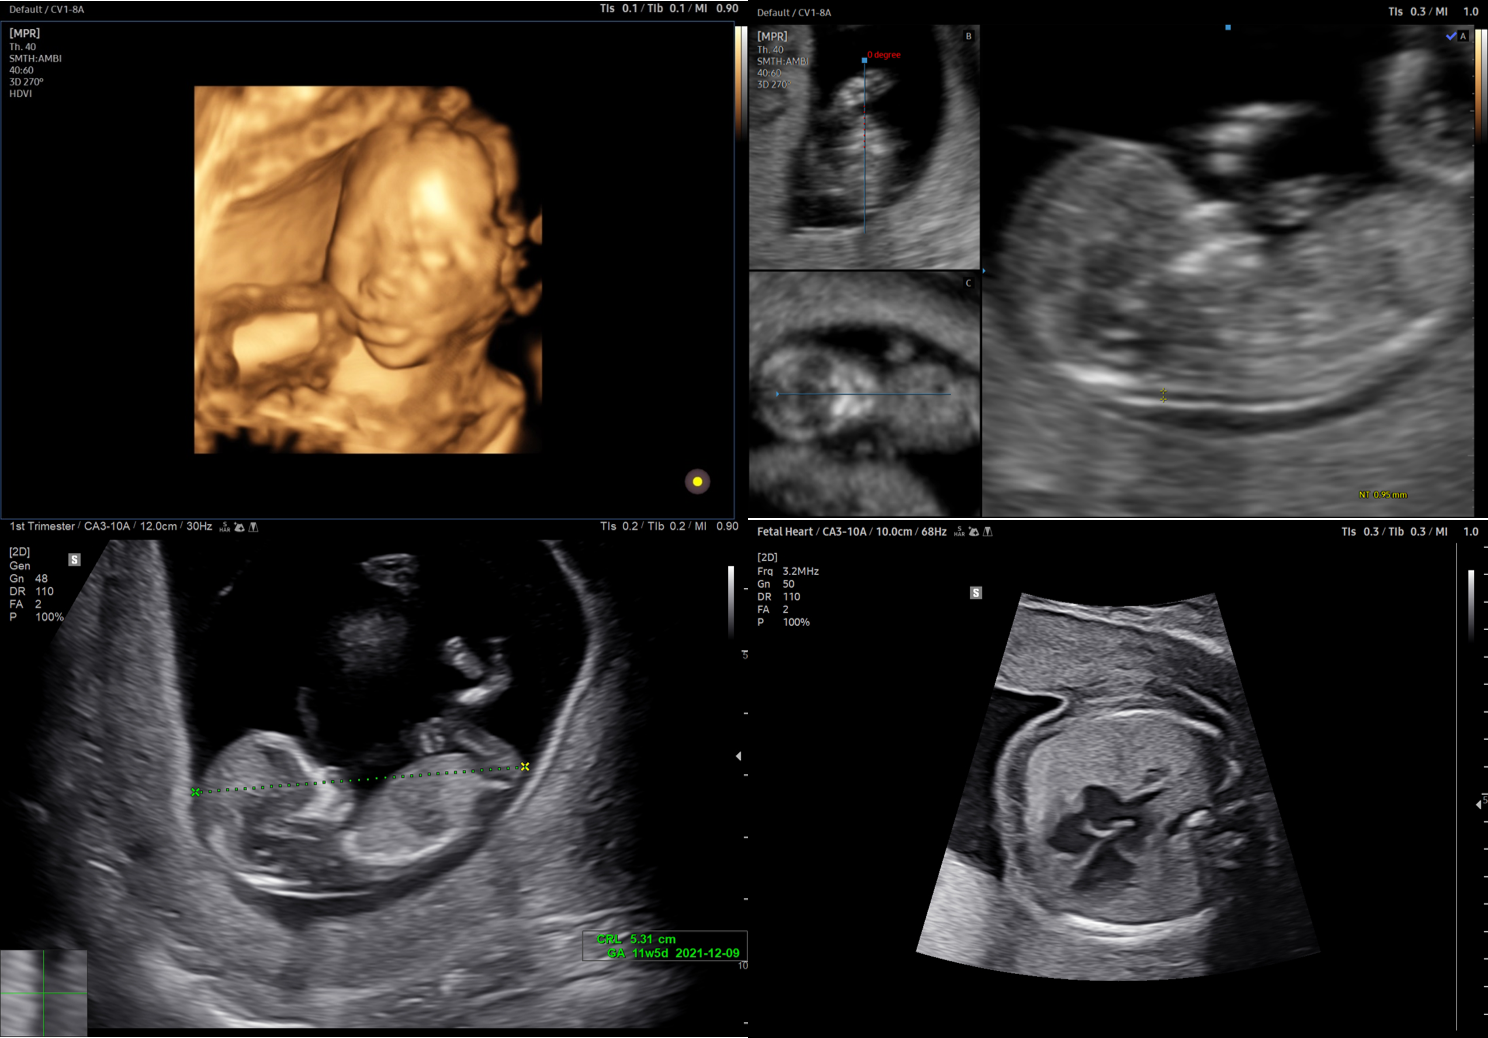

El sistema de ultrasonido V8 mejora el flujo de trabajo y el rendimiento de los pacientes en la atención médica de la mujer. Gracias a las funciones premium Crystal Architecture™ e Intelligent Assist de Samsung, el V8 ayuda a agilizar los procesos y a aumentar la confi anza incluso en exámenes femeninos complejos, además de ayudar a comunicar los resultados fácilmente a las pacientes.